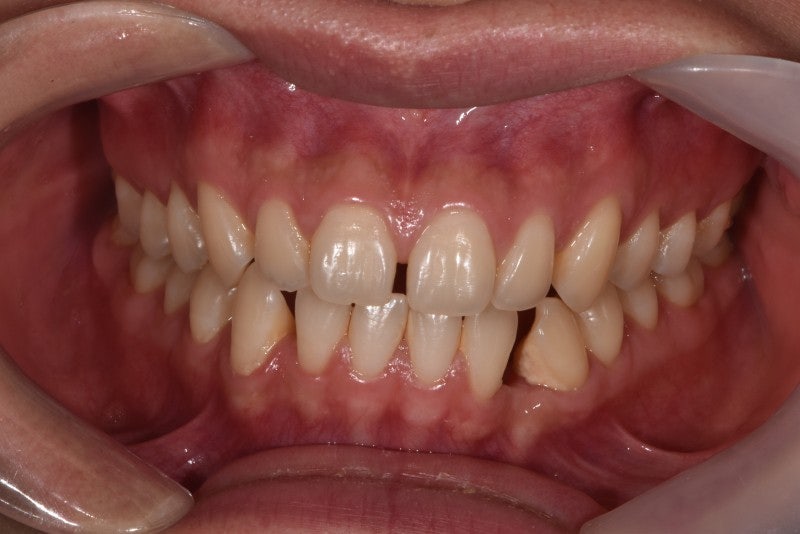

-비수술적 안면비대칭교정 사례-사례1(일측성 비대칭 상악연전)

사례 2(양측 대칭 상악 확장)